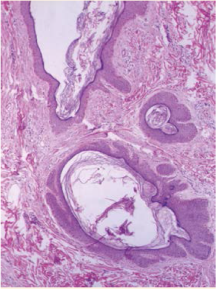

epitelio discretamente atrófico e hiperpigmentación de la capa basal, así como disminución de las glándulas sebáceas. En la dermis se observaron fibrosis discreta e infiltrado inflamatorio leve perivascular, con predominio de linfocitos y vasos capilares sanguíneos dilatados (Figuras 4y5). La correlación clínico-patológica fue de nevo comedón

Figura 4 Imagen histológica del nevo comedónico. Se observan las dilataciones foliculares que corresponde a comedones. HE40X.

En la histopatología se observan múltiples in-fundíbulos foliculares agrupados, dilatados y cubiertos con queratina lamelar, basófila y ortoqueratósica y epitelio atrófico. Las paredes del folículo están comprimidas por numerosas capas de queratinocitos y la epidermis interfolicular es papilomatosa e hiperqueratósica.1),(4 En la base de las invaginaciones foliculares pueden observarse glándulas sebáceas rudimentarias.6 Mediante microscopia electrónica puede observarse au-mento en el número de células de Langerhans y abundantes tonofilamentos en la porción supe-rior del estrato espinoso. El músculo pilo-erector muestra partículas intracelulares de glucógeno y no está completamente diferenciado.6 En análisis inmunohistoquímicos se ha demostrado aumento de la expresión del antígeno nuclear de proliferación celular, de la molécula de adhesión intercelular tipo 1, del antígeno de histocompa-tibilidad HLA-DR y la glucoproteína CD68, en la epidermis del infundíbulo piloso alargado y dilatado o en las células de la dermis más cer-cana al bulbo en proliferación.3